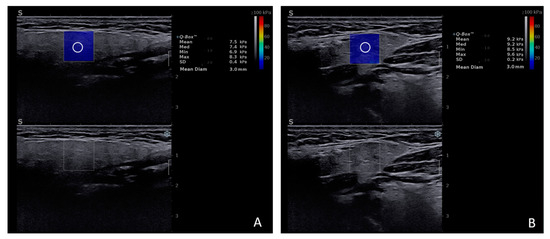

- Muntean, D.; Lenghel, M.; Ciurea, A.; Dudea, S. Viscosity Plane-wave UltraSound (ViPLUS) in the assessment of parotid and submandibular glands in healthy subjects—Preliminary results. Med. Ultrason. 2022, 24, 300–304. [Google Scholar] [CrossRef]

- Muntean, D.D.; Lenghel, M.L.; Petea-Balea, D.R.; Ciurea, A.I.; Solomon, C.; Dudea, S.M. Functional Evaluation of Major Salivary Glands Using Viscosity PLUS and 2D Shear-Wave PLUS Elastography Techniques in Healthy Subjects-A Pilot Study. Diagnostics 2022, 12, 1963. [Google Scholar] [CrossRef]